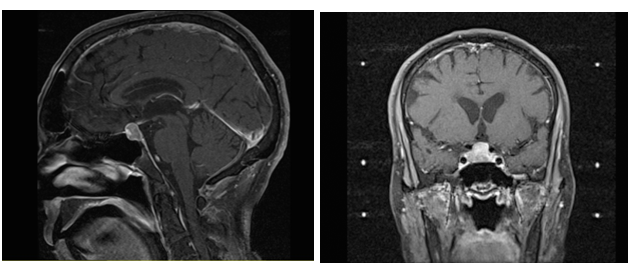

An 82-year-old male presented to an outside facility with an unrelated syncopal episode. Patient workup revealed an incidental finding of a 1.6cmx2.2cm suprasellar mass on MRI. Further assessment concluded that it was a non-secretory pituitary adenoma (Figure 1). All treatment options were then carefully reviewed and discussed with the patient and his family. A full review of the risks, benefits and alternatives were discussed with the family for options of observation, gamma knife radiosurgery and endoscopic transsphenoidal resection of the macroadenoma. The family, taking into consideration with the patient’s age subsequently chose radiotherapy. The patient underwent gamma knife radiosurgery with stereotactic localization. (Insert gamma knife radiosurgery protocol). A 14Gy was delivered to the 50% isodose line with a region measuring 2.6cc giving complete coverage but maintaining dose to the brain stem to less than 6Gy; less than 4Gy to the optic nerve and optic chiasm; and less than 50cGy to the bilateral lens.

Figure 1 A) Pre-Gamma Knife T1 Weighed MRI (Sagittal View); B) Pre-Gamma Knife T1 Weighed MRI (Coronal View).